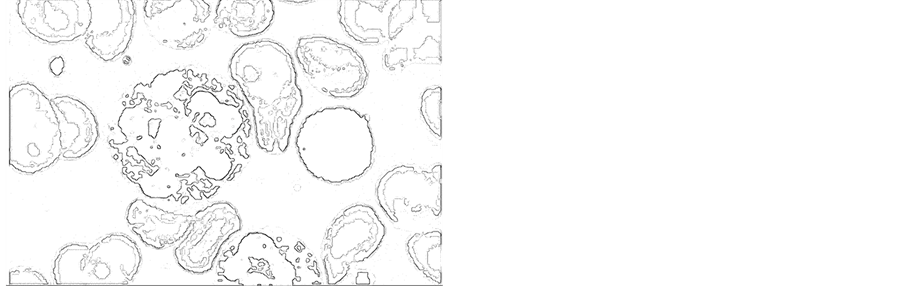

To the image in Figure 4, in Figure 2 and the image in Figure 3 we applied wavelet analysis. In Figures 5-7 shows the results of wavelet analysis.

The best result of wavelet analysis is shown in Figure 5 and Figure 6. These

Figure 5.Wavelet analysis (for Figure 2).

Figure 6. Wavelet analysis (for Figure 3).

Figure 7. Wavelet analysis (for Figure 4).

are the images for which the procedure for changing the contrast was made (see Figure 2 and Figure 3). We also see that in Fig. 6, more details are shown than in Figure 5. In Figure 6 we clearly see the internal structure of the cells. Thus, changing the contrast in the HSV model gives the best result for wavelet analysis.